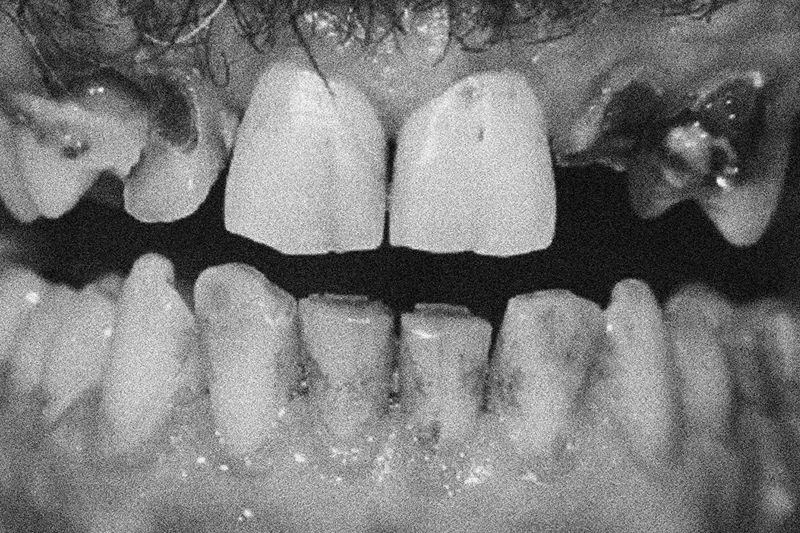

Når den almene helbredstilstand bliver dårligere, afspejles det oftest også i den orale sundhed. Både fysiske og kognitive funktionstab kan medføre ophør med regelmæssige tandplejebesøg, svigtende egenomsorg for mund og tænder med risiko for sygdomsudvikling, infektion i mundhulen og varige skader på tænderne.